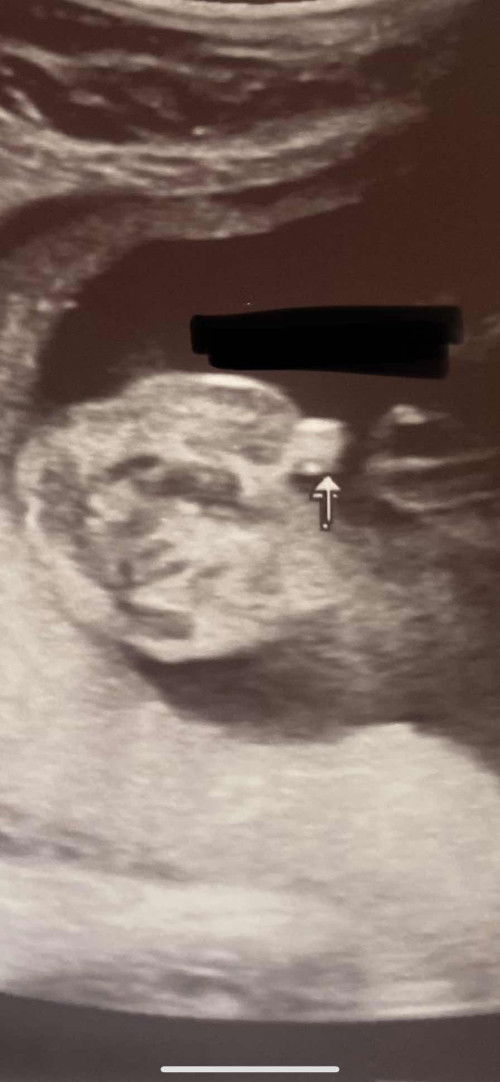

ULTRASOUND

Mga Mi pacheck naman po kung baby girl or baby boy po. Naninigurado lang po